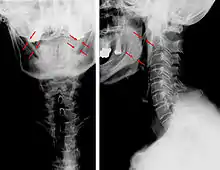

Anteroposterior and lateral radiographs of cervical spine showing ossification of the stylohyoid ligament on both sides